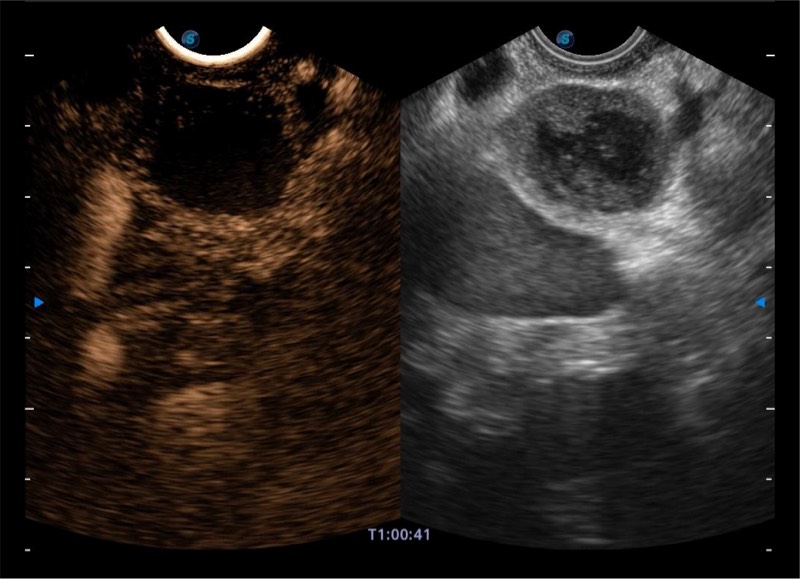

基于二十年的超声技术积累,乐玩lewin国际提供了最新一代的独立超声主机,在提供高质量图像的同时满足多学科使用。具备常见多普勒技术并提供弹性成像、声学造影等高端影像技术。新一代传感器具有更强的抗干扰能力并减少图像伪影。